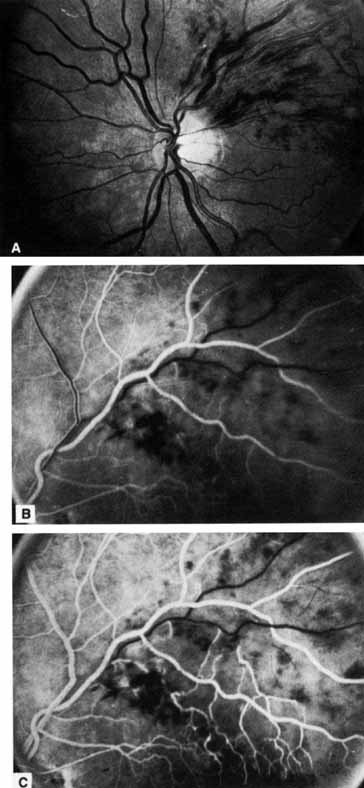

The ophthalmoscopic features of nonischemic central retinal vein occlusion are similar to those of ischemic central retinal vein occlusion, but are much less extensive (see Fig. 2; Fig. 3A and 3B). Engorgement of the venous tree (including the capillaries) is prominent; there is increased tortuosity and dilation and a darker appearance of the blood column. Retinal hemorrhages vary markedly. Sometimes they occur only peripherally; at other times, they may be rather prominent in the posterior pole.60 Cotton-wool spots are rare. Vision may be decreased because of macular edema or macular hemorrhage.

Fig. 3 A and B. Acute nonischemic central retinal vein occlusion in a 36-year-old hypertensive man. His visual acuity was 20/200. C and D. Six weeks later, he presented with eye pain, decreased vision, and neovascular glaucoma. The type of occlusion now is ischemic.

The angiographic pattern may show little except occasionally a prolonged venous transit time. Dilation of the retinal venous circulation, mild staining of the walls of veins, and varying degrees of disc and macular edema may be present (including cystoid macular edema). Capillary nonperfusion is not a prominent feature, nor is its sequela, neovascularization. The electroretinogram is nearly normal, confirming the lack of ischemia.77 The intraocular pressure is frequently lower on the side of the occlusion.78 Synonyms for this type of central retinal vein occlusion have included partial, incomplete, imminent, threatened, incipient, or impending central retinal vein occlusion.60,76 How many central retinal vein occlusions in this category are actually incomplete or partial occlusions that then progress to a more complete occlusion is unknown. It does appear that some eyes with nonischemic central retinal vein occlusion go on to develop a more ischemic type of central retinal vein occlusion (see Fig. 3); whether this represents a progression of the vein occlusion62 or simply progressive retinal capillary nonperfusion is unknown. In series in which the incidence of conversion for the nonischemic occlusion to the ischemic type has been studied, the incidence ranges from approximately 5% to 22%, depending on the duration of follow-up, and is higher for older patients.63,74,79–81

Patients with an ischemic pattern are usually aware of a sudden, painless decrease in visual acuity. Vision ranges from 20/400 to hand movements. The onset, however, is generally not as rapid or the visual loss as extensive as in central retinal artery occlusion. Exceptional cases have been noted in which patients with an acute onset had reasonably good vision and yet demonstrated a picture of ischemic central retinal vein occlusion. Patients with ischemic occlusion have an average age of 68.5 years.66 Confluent hemorrhages are the most prominent ophthalmoscopic feature of an acute ischemic central retinal vein occlusion (see Fig. 3C and 3D). These hemorrhages occur in a wide variety of shapes and sizes; they are usually concentrated in the posterior pole, but may be seen throughout the retina. Hemorrhages in the superficial retina may be so prominent about the posterior pole that the underlying retina is obscured. Many hemorrhages are flame shaped, reflecting the orientation of the nerve fibers. Dot and punctate hemorrhages are interspersed and indicate involvement of the deeper retinal layers. Bleeding may be extensive, erupting through the internal limiting membrane to form a preretinal hemorrhage or extending into the vitreous. Small dot hemorrhages may be seen either isolated or clustered around small venules. The entire venous tree is tortuous, engorged, dilated, and dark. The retina is edematous, particularly in the posterior pole; some of this edema may obscure portions of the retinal vessels. Cotton-wool patches (soft exudates) are often present.